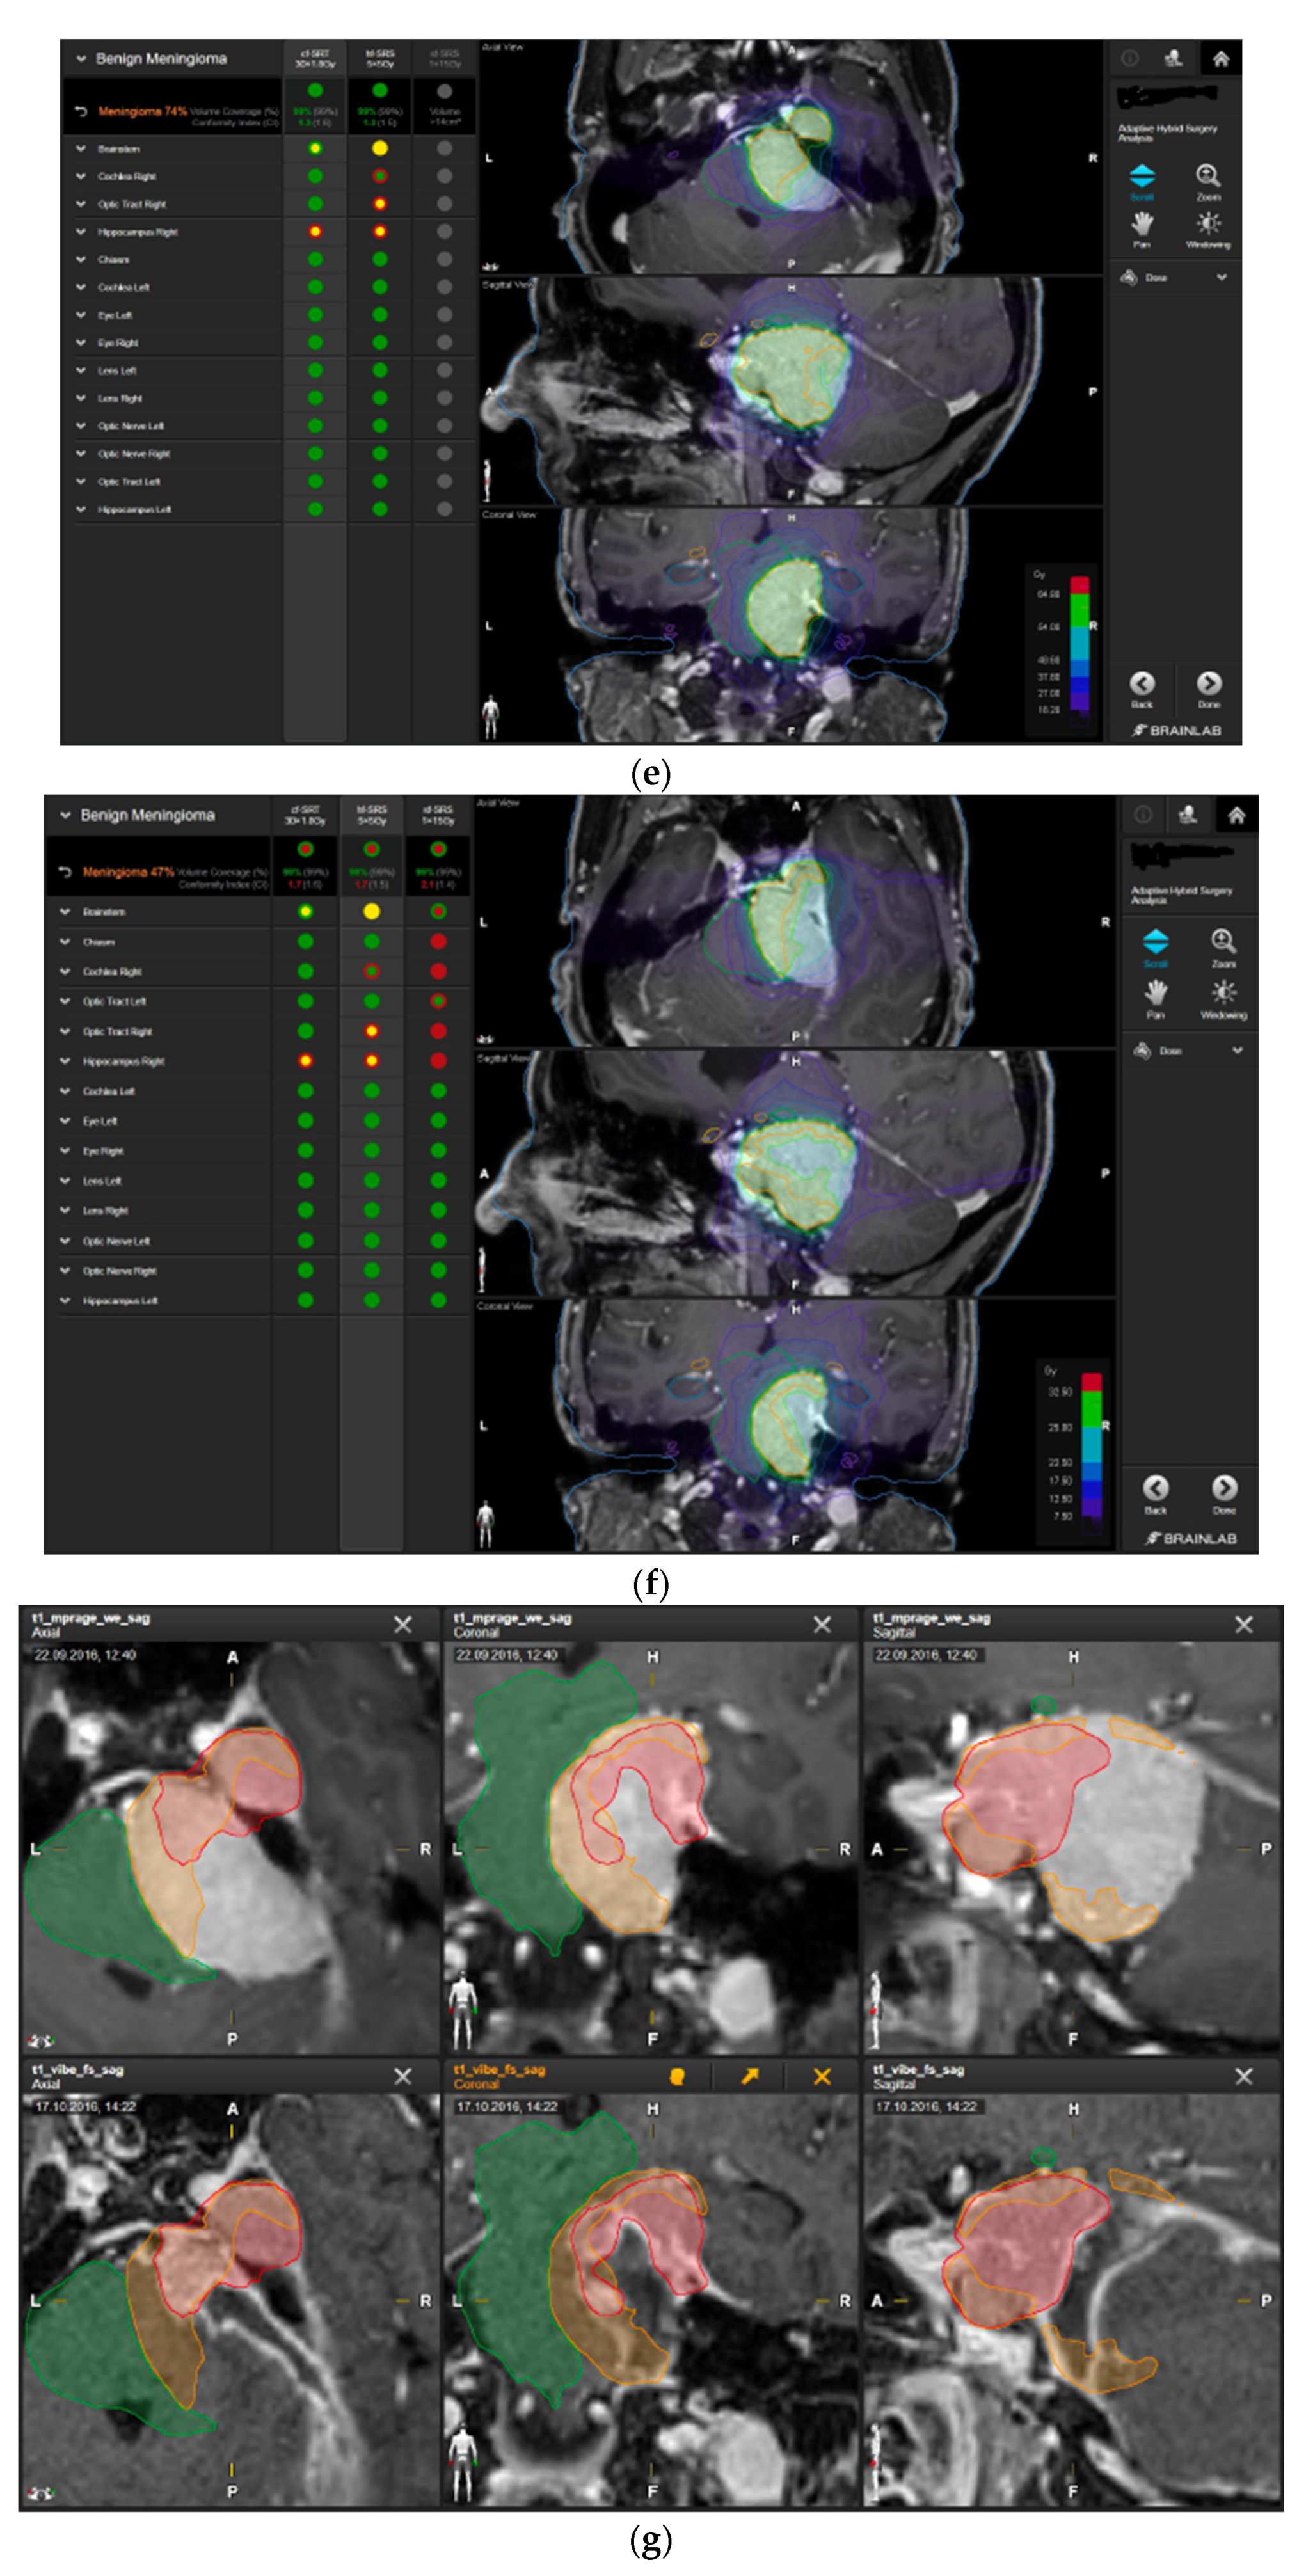

A 58-year-old female presented with progressive headache, difficulty swallowing, diplopia, hearing loss, and reduced face sensitivity on the right side (Figure 4). Elective craniotomy and AHSA-assisted tumor resection were performed. The patient underwent hypofractionated radiosurgery (5 × 5 Gy) of the residual meningioma one year after tumor resection.

Figure 4.

Second representative case of AHSA-supported tumor resection. (a) MRI imaging of petroclival meningioma (axial, coronal, sagittal). (b) Depiction of preoperative tumor volume (orange) and planned residual tumor volume (red). (c) AHSA summary table showing the stereotactic radiation constraints for the preoperatively planned residual tumor volume. With this plan, conventional fractionation and hypofractionation were feasible with effective tumor coverage.

—brainstem: mean dose is safe, while the max. dose is marginally safe;

—right optic tract: mean dose unsafe, max. dose is marginally safe;

—right hippocampus: marginally safe, and mean dose unsafe, max. dose is marginally safe. (d) First intraoperative structure update (ISU) with a residual tumor volume of 82% with the calculated dose constraints for conventional and hypofractionated radiotherapy. Single dose stereotactic radiosurgery was not feasible with this degree of remaining tumor. At this point, the dose constraints for conventional radiotherapy were:

—brainstem: mean dose is safe, max. dose is marginally safe;

—right hippocampus: mean dose unsafe, max. dose is marginally safe. Hypofractionated radiotherapy:

—brainstem: marginally safe;

—right cochlea: mean dose unsafe, max. dose safe;

—right hippocampus: mean dose unsafe, max. dose is marginally safe. (e) Second intraoperative ISU with residual tumor volume of 74% and calculated dose constraints for hypofractionated radiotherapy. Single dose stereotactic radiosurgery was still not considered feasible with this residual tumor volume. The dose constraints for organs at risk for conventional and hypofractionated radiotherapy were unchanged compared to the first ISU. (f) Third intraoperative ISU with residual tumor volume of 47% and calculated dose constraints for conventional, hypofractionated radiotherapy, and radiosurgery. The current dose constraints for organs at risk were the following for conventional radiation:

—right hippocampus: mean dose unsafe, max. dose is marginally safe. Hypofractionated radiation, which was unchanged for the first and second ISU:

—right hippocampus: mean dose unsafe, max. dose is marginally safe. For single fraction radiosurgery, the OAR dose constraints were available but considered to be unsafe.

—brainstem: mean dose unsafe, max. dose safe;

—chiasma: unsafe;

—right cochlea: unsafe;

—left optic tract: mean dose unsafe, max. dose safe;

—right optic tract: unsafe;

—right hippocampus: unsafe. (g) Overlay of preoperatively estimated and intraoperative effective residual tumor volume in AHSA. (h) Final intraoperative dose constraints after last ISU and data fusion with intraoperative CT. The dose constraints for OARs appeared to improve and were as follows for conventional and hypofractionated radiotherapy: